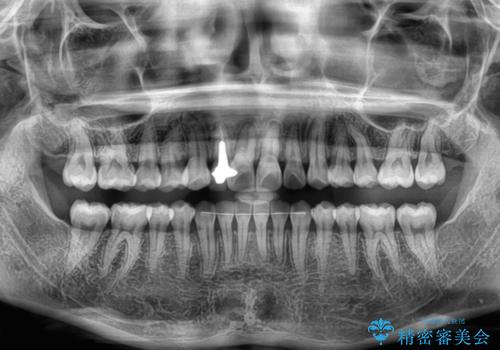

- 上下前歯のデコボコを気にして来院された患者様です。

インビザラインによる上下歯列の拡大と、IPR(歯と歯の間を削る)にるスペースの獲得により、前歯のデコボコを改善することとしました。

下顎前歯は後戻りを起こしやすいため、舌側を細いワイヤーで固定し、マウスピース型リテーナーで保定を行うこととしました。